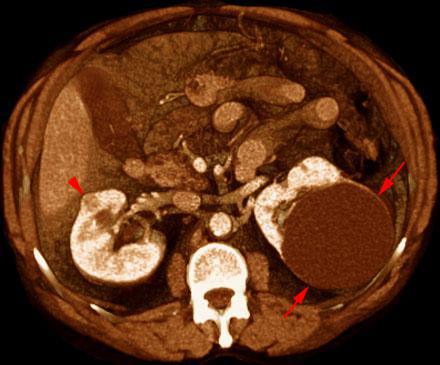

Pequeño hipernefroma

VR seccional. Visión axial caudal. En estudio de TC abdominal contrastado en fase venosa, junto a un quiste renal simple (flechas) incidentalmente se visualiza un pequeño nódulo cortical renal derecho (punta de flecha) con captación de contraste